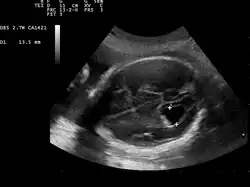

| Prenatal ultrasound showing a well defined hypoechoic lesion corresponding to a choroid plexus cyst | |

Choroid plexus cysts (CPCs) are cysts that occur within choroid plexus of the brain. They are the most common type of intraventricular cyst,[1] occurring in 1% of all pregnancies.[2]

It is believed that many adults have one or more tiny CPCs.[3] The fetal brain may create these cysts as a normal part of development. They are temporary and usually are gone by the 32nd week of pregnancy.[4]

CPCs can form within this structure and come from fluid trapped within this spongy layer of cells, much like a soap bubble or a blister. CPCs are often called "soft signs" or fetal ultrasound "markers" because some studies have found a weak association between CPCs and fetal chromosome abnormalities.